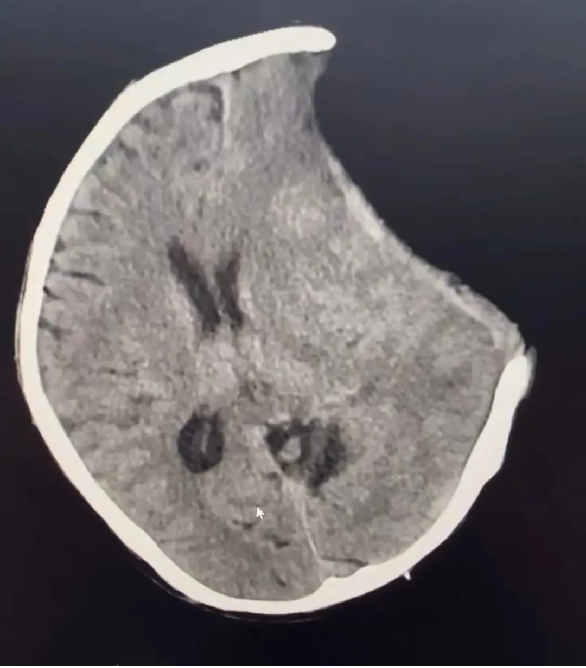

患者汪某,男性,66歲,因重症顱腦(nǎo)損傷,多發肋骨(gǔ)骨折,血氣胸,鎖骨骨折辦理入院緊急手術,醫院神經外科專家團隊為患者行開顱血腫清除+大骨瓣減壓術。手術順利,術後(hòu)恢複滿意。專家團隊將患者手術去除的顱骨骨瓣進行了清洗、滅菌後低(dī)溫冰凍儲存。

患者術後滿三個月(yuè)再次返院進(jìn)行顱骨缺損(sǔn)修補術,經過完善術前檢查、全(quán)科討論、做好充分手術(shù)準備後,武(wǔ)寧縣總醫院人民醫院院區神(shén)經外科團隊成功為患者完成(chéng)自體顱骨修補術(shù)。

術前: